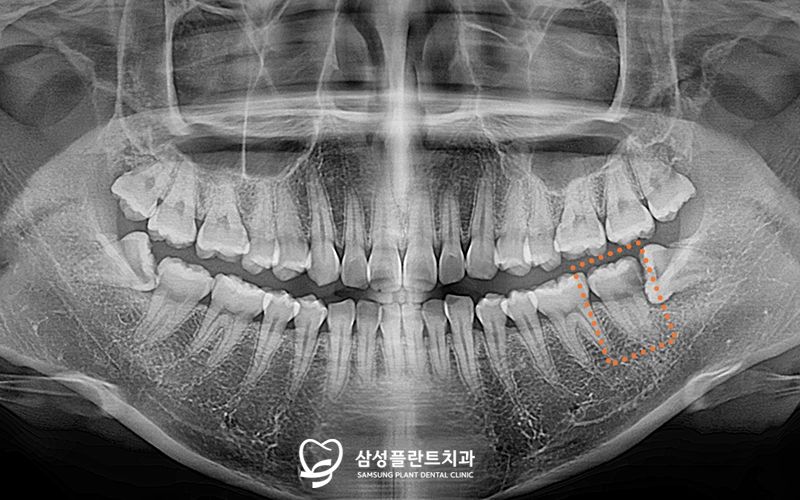

✅ 초진

오늘 소개해드릴 분은

충치가 있는 것 같고,

전체적으로 이가 욱씬거린다며

본원을 찾아주셨는데요.

검진을 해보니,

전체적으로 잇몸이 부어있었고

4개의 사랑니와

왼쪽 아래 큰 어금니의 충치를

관찰할 수 있었습니다.

엑스레이 사진 촬영 후

사랑니의 위치 및 방향을

꼼꼼하게 체크해보았는데요.

아래쪽 2개는 기울어지고

일부가 매복된 상태로 자리잡고 있었고,

왼쪽 아래 두번째 큰 어금니의 인접면엔

사랑니로 인해

충치가 생긴 상태였답니다.